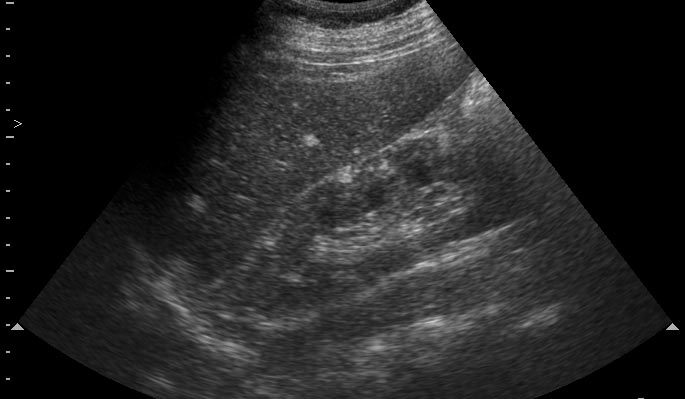

Парень 16 лет с эпилепсией. Изменения почек симметричные с обеих сторон. Ваши рекомендации?

УЗи почек - туберoзный склероз (болезнь Бурневиля)

Мысль пока появилась одна: Болезнь Бунневиля (Туберoзный склероз), рекомендация: МРТ головного мозга.

В паренхиме поллиморфные гиперэхогеные очаги по типу ангиолипоматоза.Учитывая двустороннее поражение,да еще умственную отсталость,то возможна врожденная патология,которую Марио уже назвал( я бы остановилась просто на ангиолипоматозе

)

Простите,не умственная отсталость,а судороги

Все верно, туберoзный склероз. На сонограммах определяются образования типа ангиомиолипом/гемангиом почек/печени. Наличие судорог редполагает сходные изменения головного мозга - доказано на КТ.